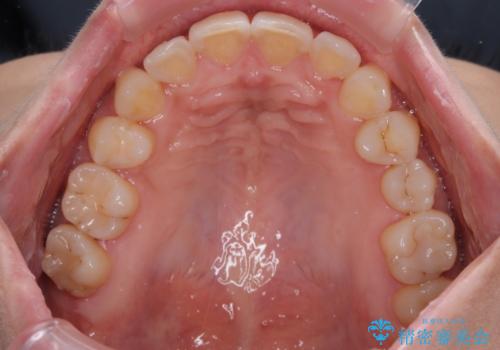

目立つ八重歯を改善 ワイヤー装置での抜歯矯正

上顎の正中位置をほぼ保った状態で、綺麗に仕上げることができました。